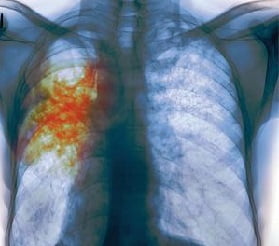

Диагноз этого опасного заболевания ставит только врач. Для определения болезни необходимо рентгенологическое исследование. Также, для диагностики туберкулёза лёгких исследуют мокроту на наличие микробактерий туберкулёза. На туберкулёз у детей может указывать положительная проба Манту. В некоторых случаях, для достоверности берется анализ крови.